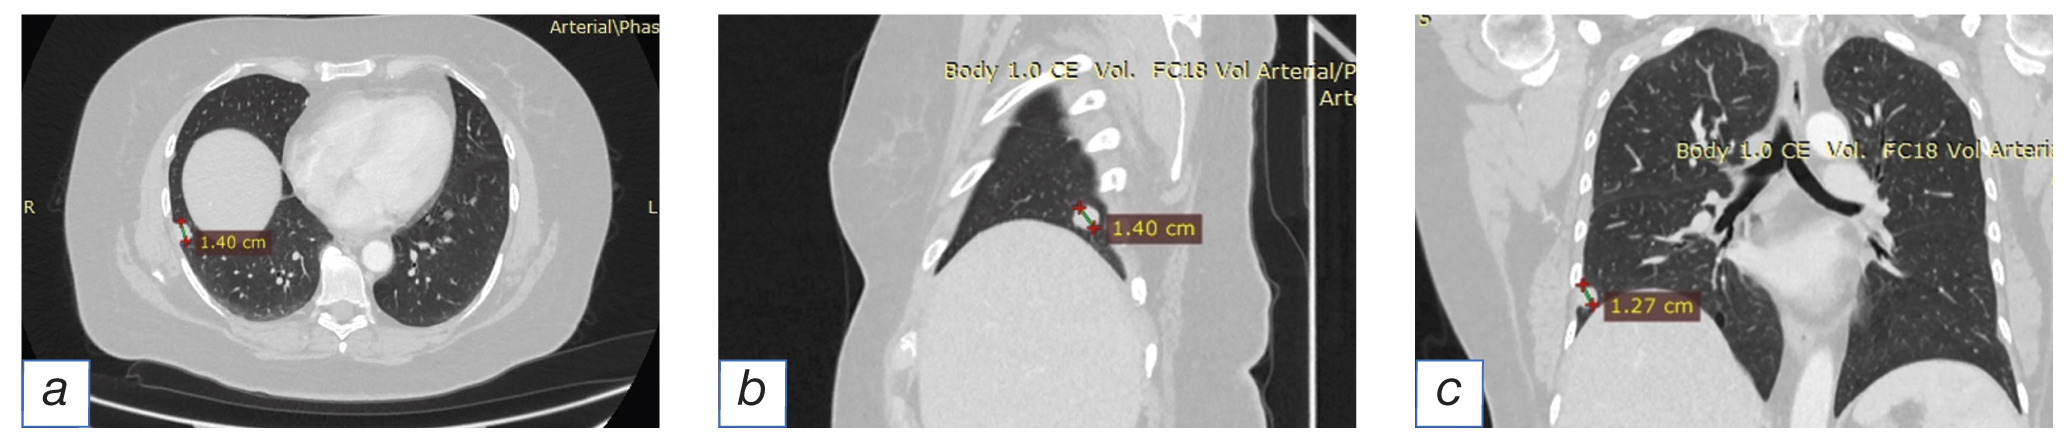

Computed tomography of the chest cavity organs with contrasting (Fig. 1): in segments S8/9 of lower lobe of the right lung, there is a subpleural solid mass (in the lower lobe of the right lung) with the dimensions of 14×11 mm.

Fig. 1. Computed tomography of the chest cavity organs: solid solitary focus in the lower lobe of the right lung for axial (а), sagittal (b) and frontal (c) projections.